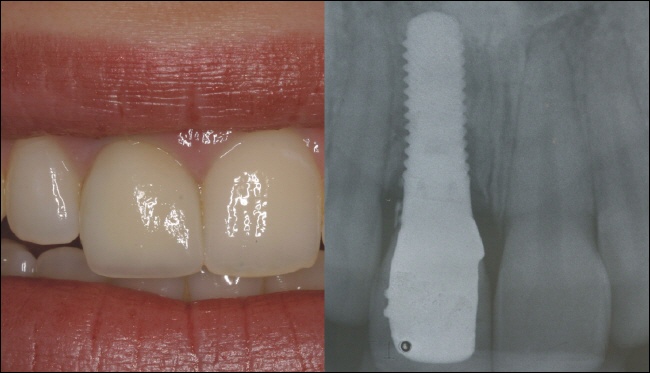

Sofortversorgung

Am folgenden Tag wird eine provisorische Krone auf das Implantat eingesetzt (links). Die Röntgenkontrolle (rechts) zeigt den perfekten Sitz der Krone. Sie ist vor allem ein ästhetischer Ersatz, da Belastungen in der Einheilphase möglichst vermieden werden sollten, um ein erfolgreiches Einheilen des Implantates zu gewährleisten. Nach der Einheilzeit wird unter ästhetischen und funktionellen Gesichtspunkten eine definitive Krone hergestellt.